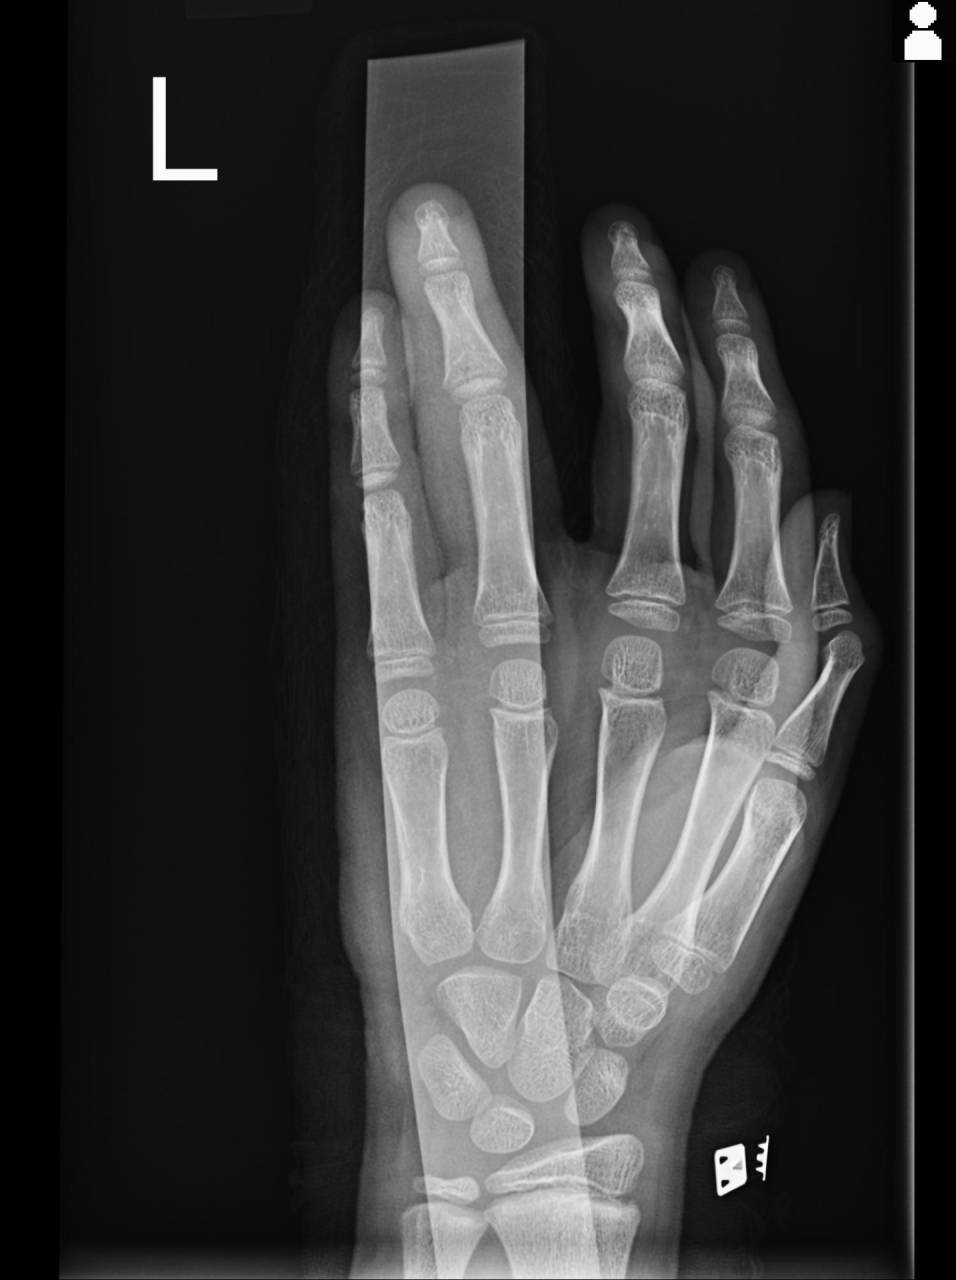

小学6年生男子、バスケットボールで遊んでいてパスを受けようとしたらキャッチミスをして左薬指(左第4指)に突き指した形で怪我をした。

外見上は腫脹があり、PIP関節付近が変形していました。

左第4指のPIP関節は20度程しか屈曲ができず、伸展も10度程しかできないとのことでした。

圧痛は中節骨基部にあり、外見上の変形している位置と同じ部位にあります。

エコーで確認をすると骨の不連続性が確認でき、骨折の可能性が高くなったので当整骨院が提携している病院にてレントゲン検査を依頼しました。

撮影した画像を確認すると中節骨基部に骨折が確認でき、骨折として施術をしていきます。